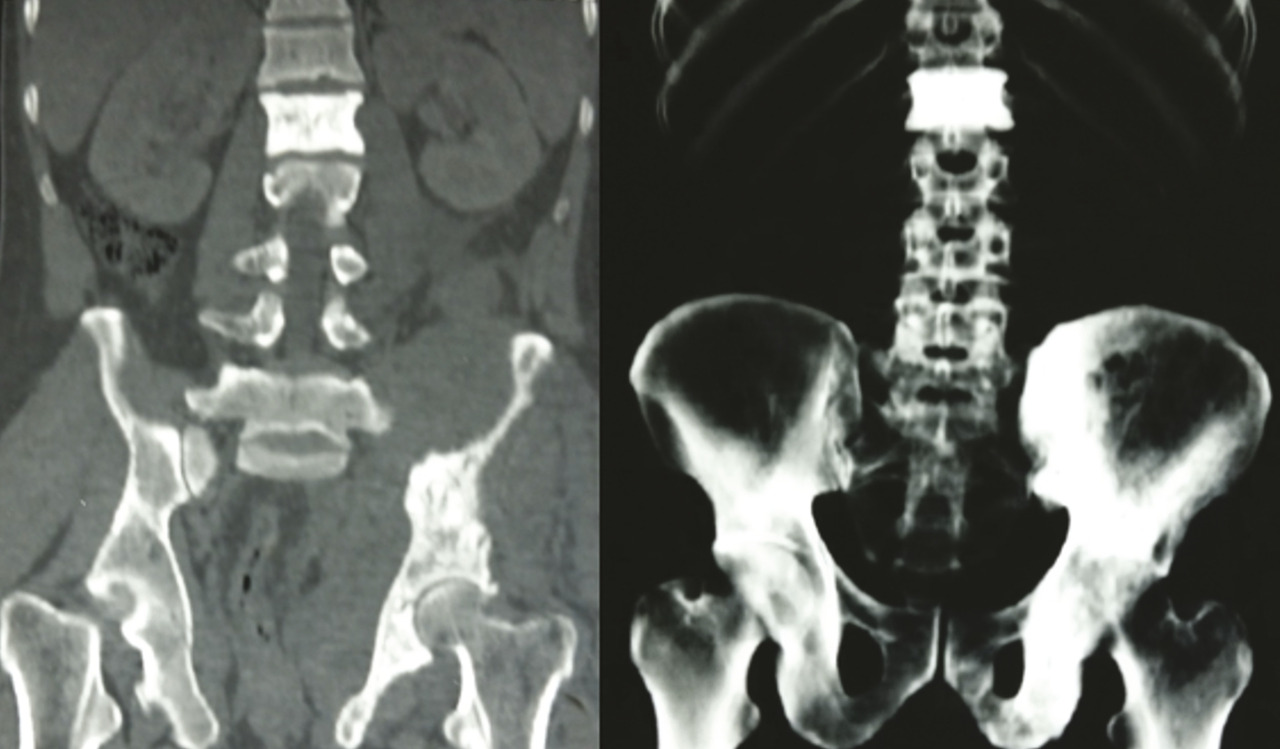

Les radiographies standards mettent en évidence une vertèbre ivoire L1 ainsi qu’une ostéocondensation de l’os iliaque gauche (fig. 1 ). Le scanner thoraco-abdomino-pelvien montre une atteinte osseuse mixte de l’aile iliaque gauche (fig. 2 ), un envahissement des parties molles (avec augmentation des volumes des muscles fessiers et du psoas [fig. 3 ] expliquant la sciatalgie), une néphromégalie unilatérale, une splénomégalie nodulaire et de multiples adénopathies abdomino-pelviennes et thoraciques.

Les radiographies standards mettent en évidence une vertèbre ivoire L1 ainsi qu’une ostéocondensation de l’os iliaque gauche (

Sur les clichés conventionnels, on décrit trois types de lésion : lytique (la plus fréquente avec 50 à 80 % des cas)2, condensante et mixte. L’ostéocondensation isolée est rare (5 % des cas).9 Elle peut réaliser l’aspect classique de la vertèbre ivoire qui est plus fréquemment rencontré dans le lymphome de Hodgkin que dans les lymphomes non hodgkiniens.2 L’association d’une lésion osseuse et d’une importante infiltration des tissus mous en regard alors que la corticale est conservée ou finement mitée est évocatrice du lymphome.9 Dans les cas où l’infiltration lymphomateuse est confinée à la cavité médullaire, les radiographies standards peuvent être normales. La tomographie par émission de positons est l’examen de référence pour evaluer les atteintes osseuses et extra-osseuses.